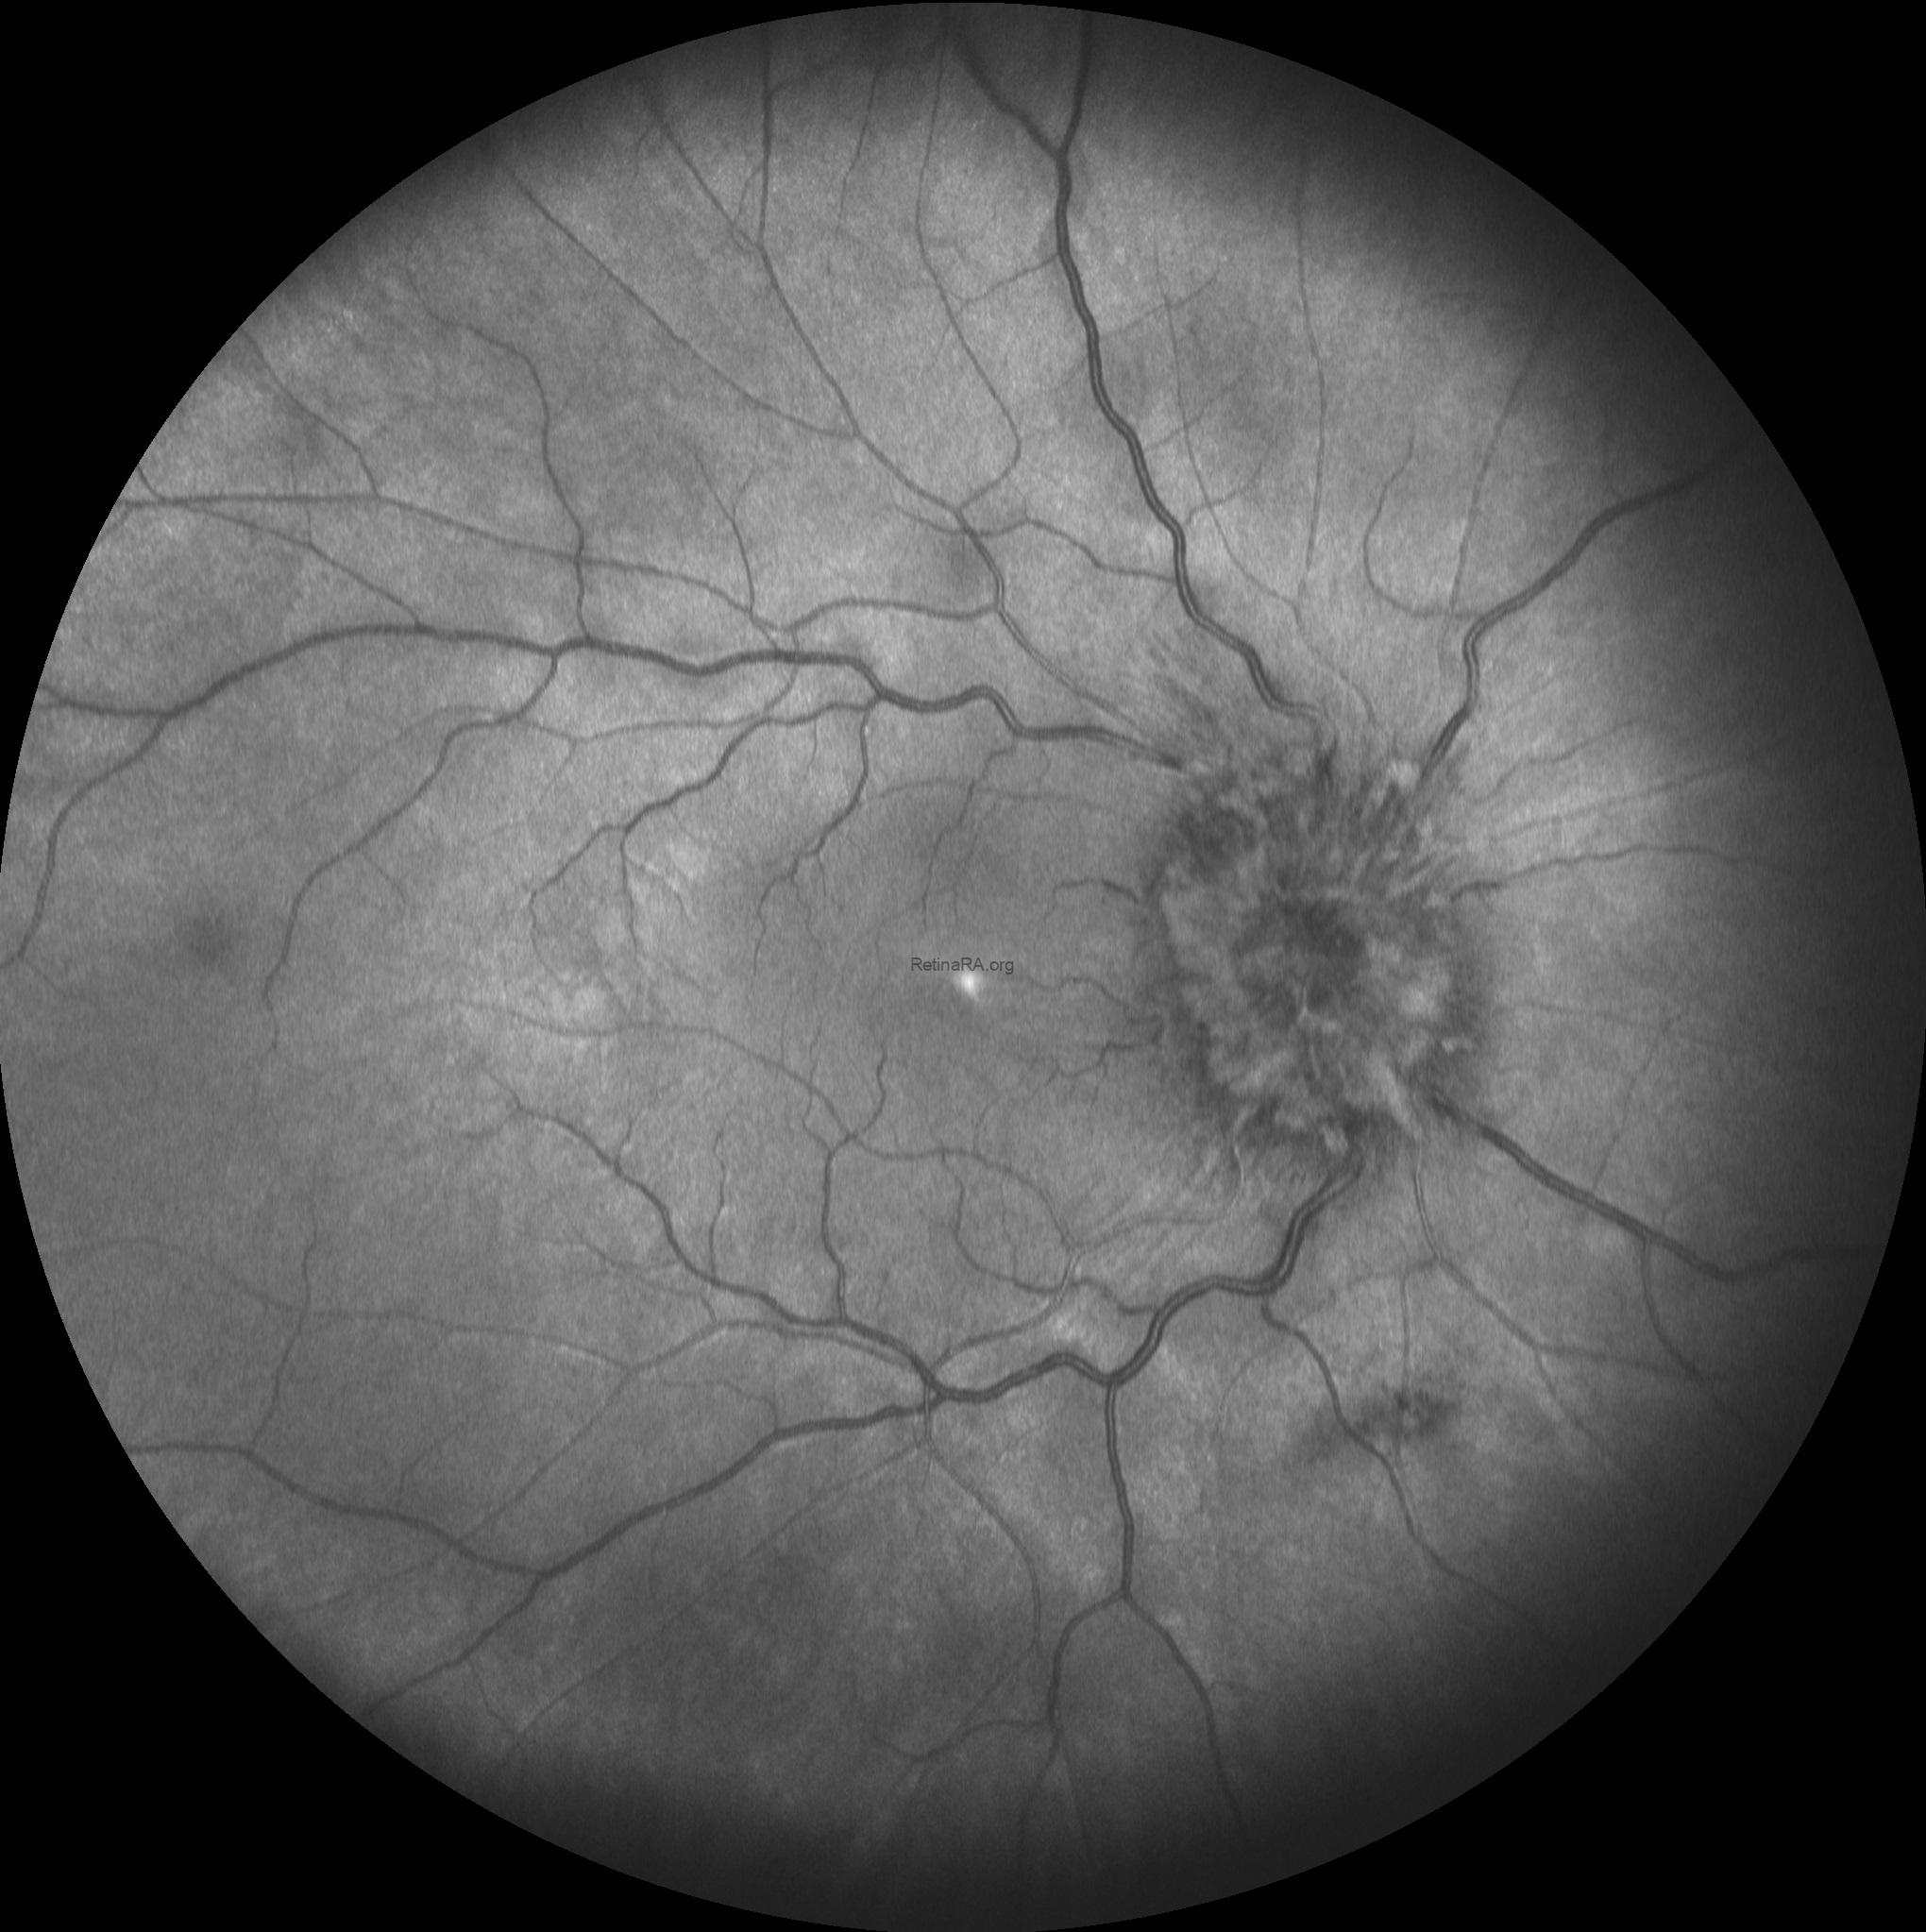

Multicolor and infrared fundus images revealed bilateral severe optic disc swelling, elevation of the disc with blurred margins, smoothly demarcated peripapillary halo, optic nerve head hyperemia, peripapillary hemorrhages, and obscuration of cup and major vessel (Grade 5 according to Frisén Scale).

Based on the optic disc appearence, the patient was diagnosed as severe papilledema and consulted to the neurology department. After neurological asessment including craniyal computed tomography the patient was diagnosed as glioblastoma multiforme.